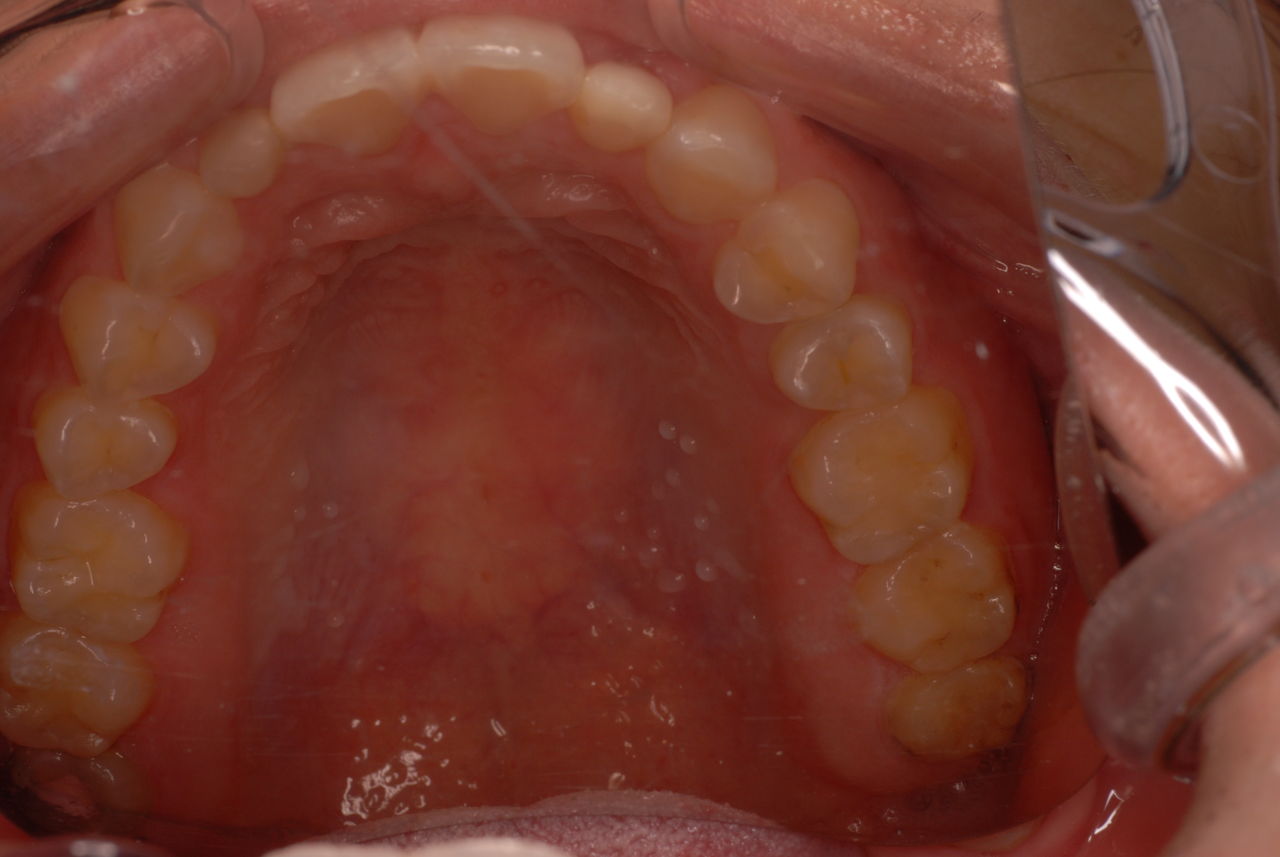

30代の男性の方です。

入れ歯を入れていました。歯科医院で歯を抜けず仕方なく入れ歯にしたとか。何とかならないものだったのか悔やまれました。

抜いた歯はありません。

一応差し歯にしましたが、歯茎の状態はよくはありません。

とりあえず希望を入れて差し歯にしたような感じです。